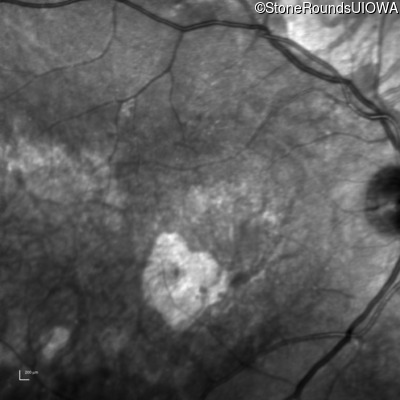

Infrared Fundus Photograph - Left - 20/80

Exemplar